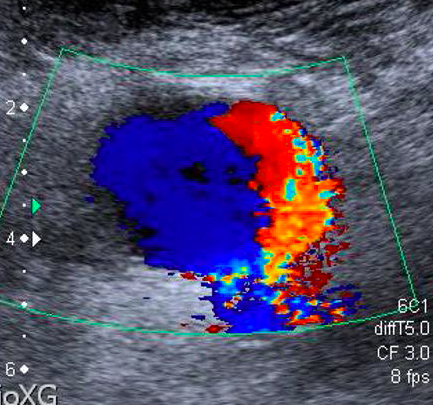

Patient undergoes LE arterial DUS. You come across an isolated image from region near femoral artery (shown below) while reading the study. No further images of the finding are available.

Swirling pattern w/ sack off of common femoral artery should make you think of PSA* (but it is not diagnostic)

pw doppler imaging showing bidirectional flow in sack attached to CFA is pathognomonic of PSA